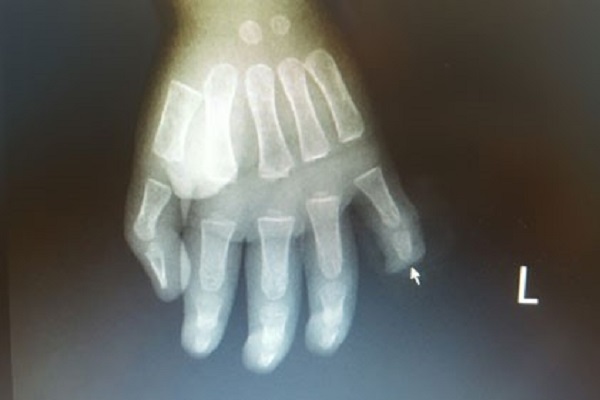

Bố mẹ lơ là, trẻ 17 tháng tuổi đứt rời đốt ngón tay do nghịch dao

- Các bác sĩ bệnh viện Việt Nam Thụy Điển Uông Bí (Quảng Ninh) vừa phẫu thuật cho một bệnh nhi 17 tuổi đứt lìa đốt trên của ngón tay út sau khi nghịch dao.